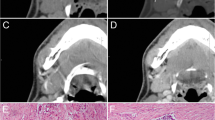

As shown in Fig. 2, myxomas had lower normalized T1-weighted signal intensity values than myxofibrosaromas (p = 0.006, Wilcoxon rank sum test), and AUC was 0.713 as shown in Fig. 3. Figure 4 shows the T1 SI of the myxofibrosarcomas by tumor grade. There was no substantial difference in the T1 SI between the myxofibrosarcomas by tumor grade (Kruskal-Wallis p = 0.88). The radiomics features for all the subjects were demonstrated in Fig. 5. The classification model built upon radiomic features obtained an AUC of 0.885 (accuracy = 0.839, sensitivity = 0.852, specificity = 0.828), which outperformed the classification model built upon the T1SI values (p = 0.039, DeLong test), and the classification model built upon volume features (AUC = 0.838, p = 0.285 by DeLong test) as shown in Fig. 3.

Discussion

The results show that the T1SI of myxofibrosarcomas are on average higher than that of myxomas, however, there was significant T1SI overlap for both lesions. We hypothesize that a more cellular tumor has higher protein content, and would therefore result in increased T1 shortening (higher T1 signal) as our results have shown. An alternative explanation is that these malignant lesions may contain small foci of hemorrhage. Myxofibrosarcomas also tended to have volumetric features that were slightly different than myxomas. Myxofibrosarcomas have been noted to have a “tail sign” and have a known propensity for spreading along the myofascial planes [18, 21]. This feature may have been detected as part of the volumetric features.

Radiomic (texture) features were the best for differentiating myxofibrosarcomas from myxomas. Quantitative analysis using a classification model based on radiomic features outperformed the classification models using volume-based and T1SI value analysis. Myxomas tend to be more paucicellular and bland (unless a cellular myxoma), and therefore have less T1 signal heterogeneity. T1-weighted signal heterogeneity of myxofibrosarcomas was greater than that for myxomas, and we speculate that the T1-weighted signal intensity heterogeneity mirrors the intrinsic histologic tumor heterogeneity seen in myxofibrosarcomas and possibly intratumoral hemorrhage.